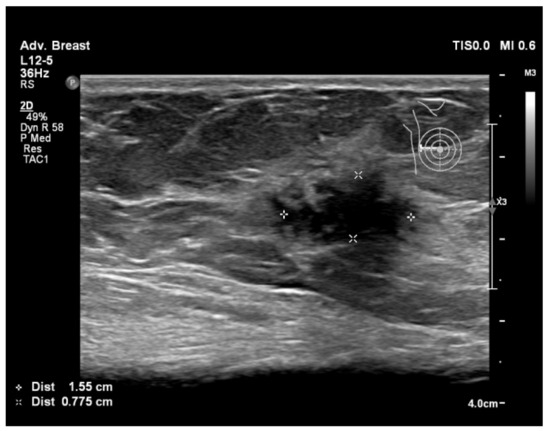

6.1. Characterization of Lesions

6.2. Real-Time Imaging and Guided Biopsies